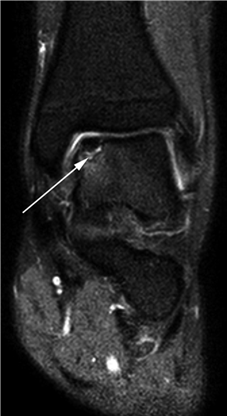

Clinical & Radiographic Imaging Archive